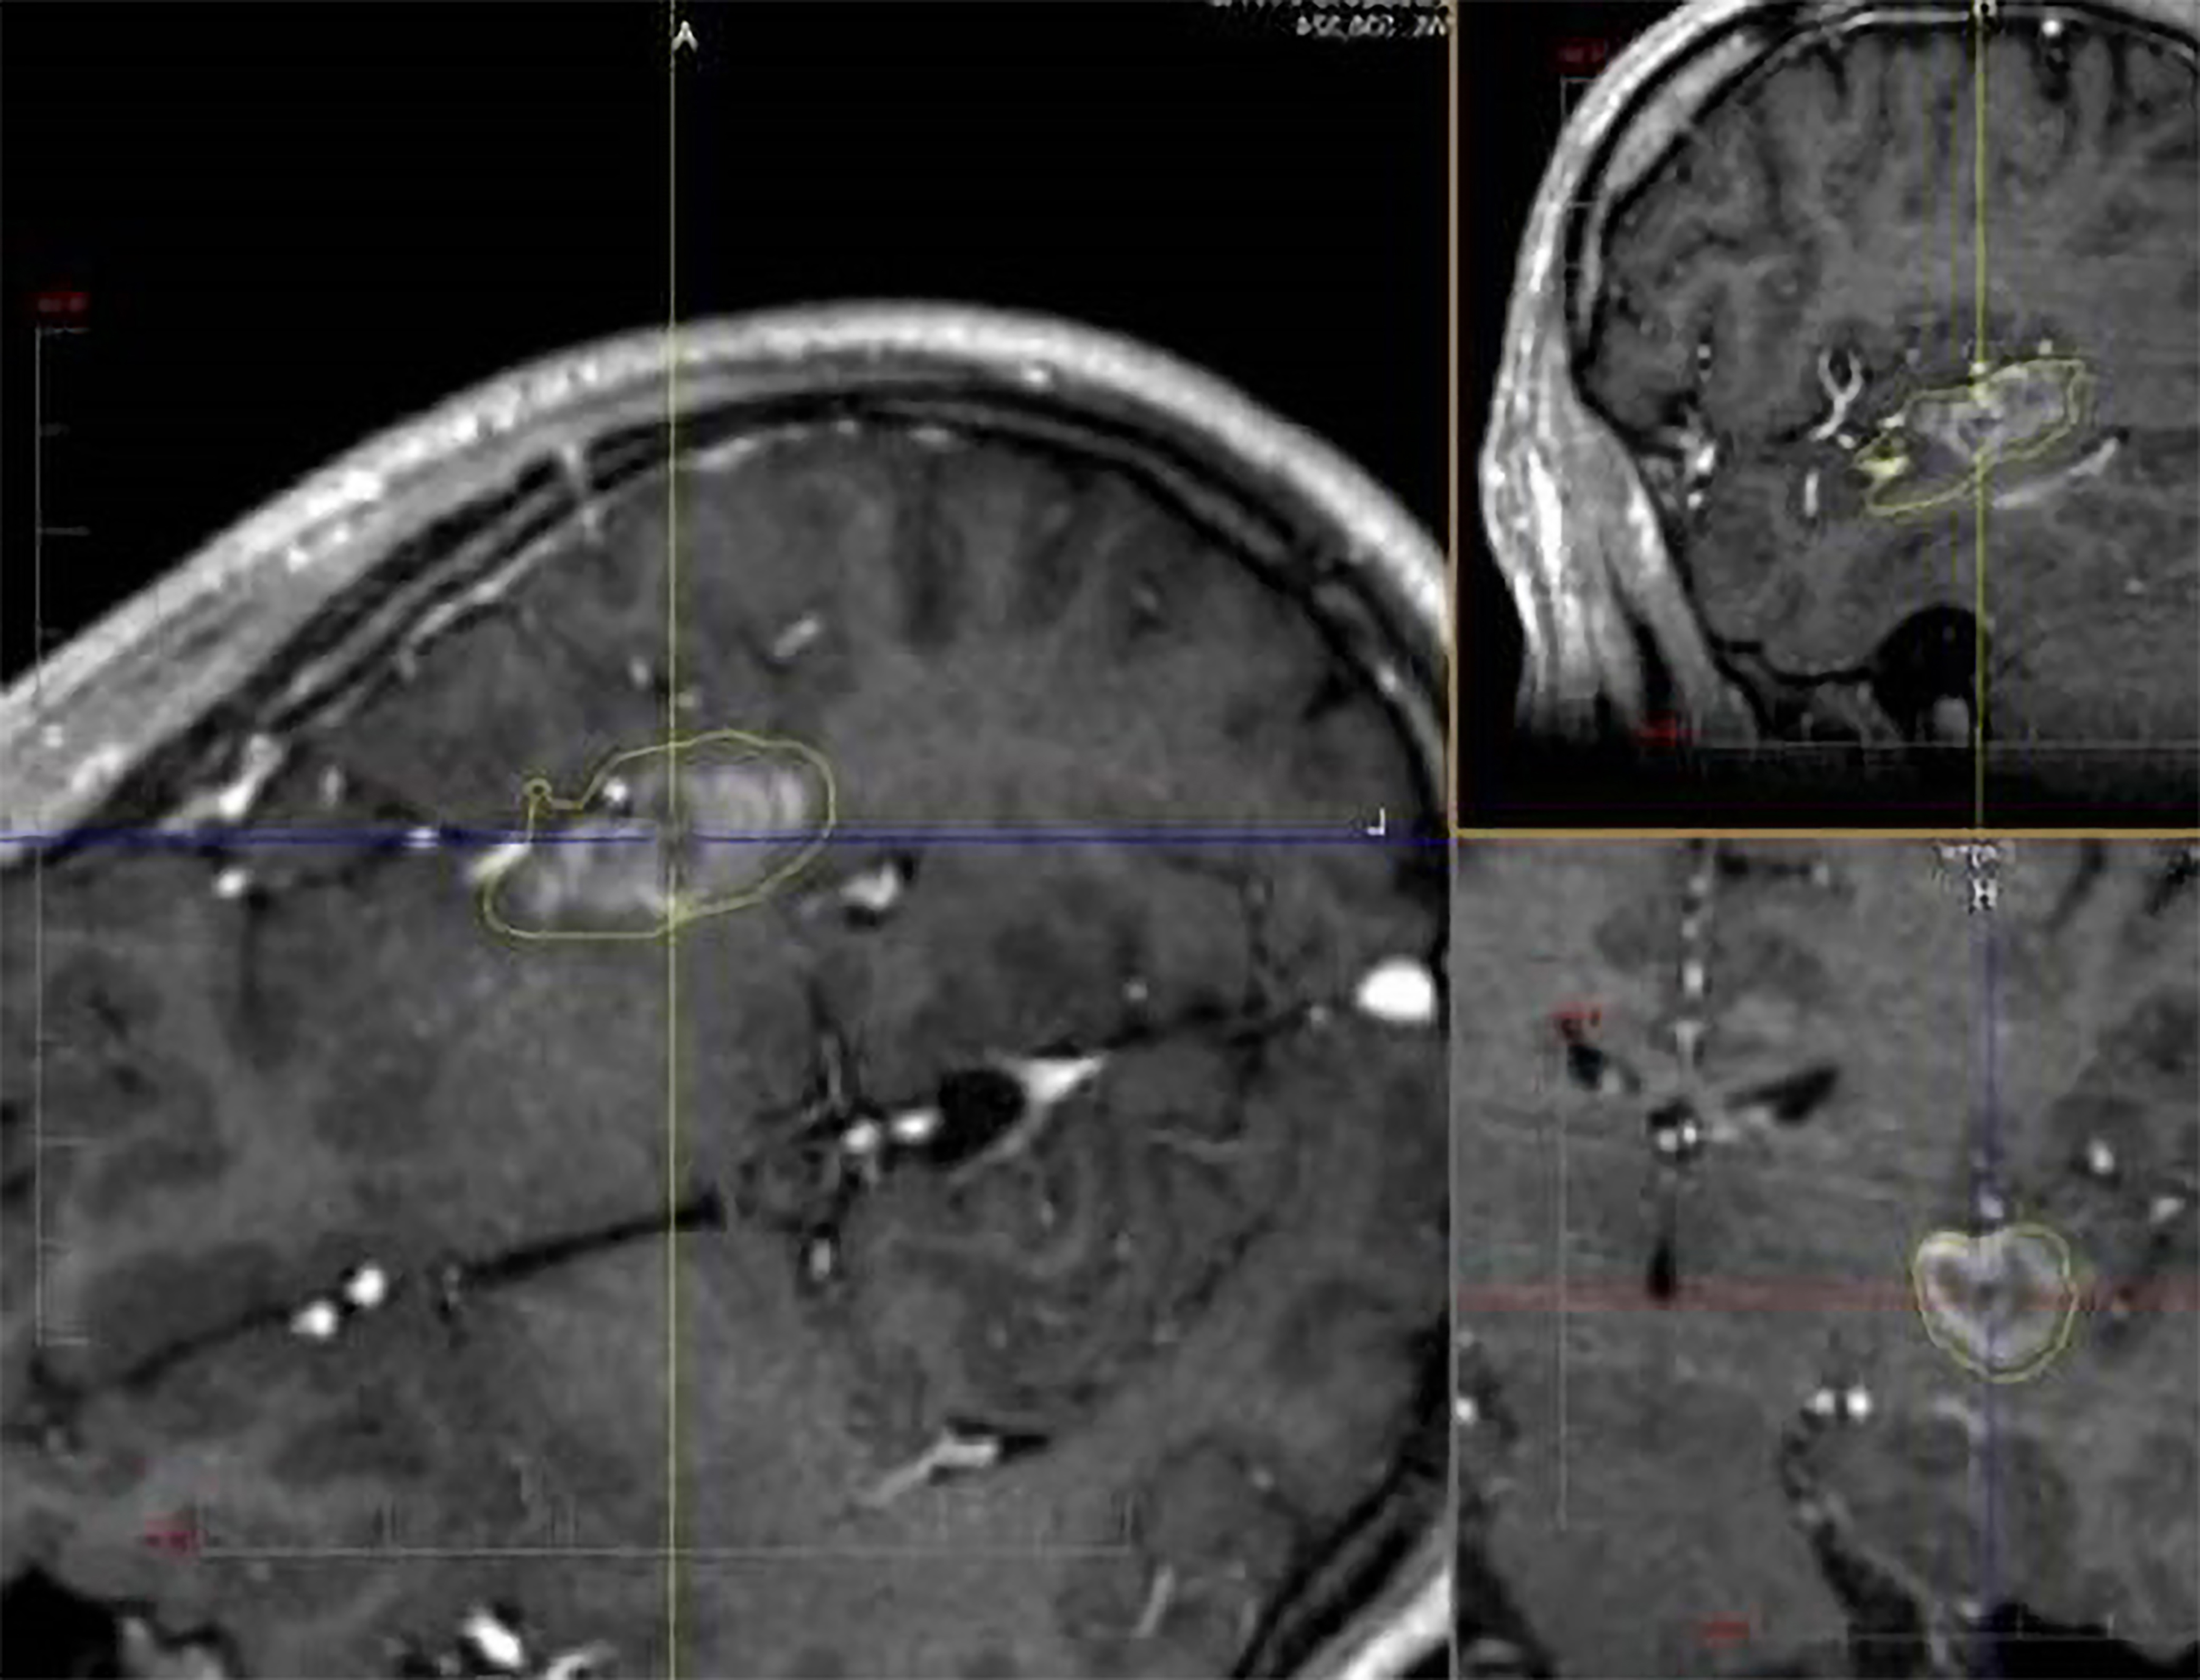

Another surgical approach to insular epilepsy is laser interstitial thermal therapy (LITT) (Fig. 3), first utilized for temporal lobe epilepsy in 2014 [39]. LITT is a minimally invasive procedure where a laser diode is inserted through a small cranial opening. The laser’s light is absorbed by the surrounding tissue, increasing heat and resulting in thermal ablation [40].

Fig. 3.

SEEG-guided laser ablation of the posterior insula in a patient with medically refractory epilepsy. The procedure was well tolerated and results in seizure freedom. SEEG, stereoelectroencephalography.